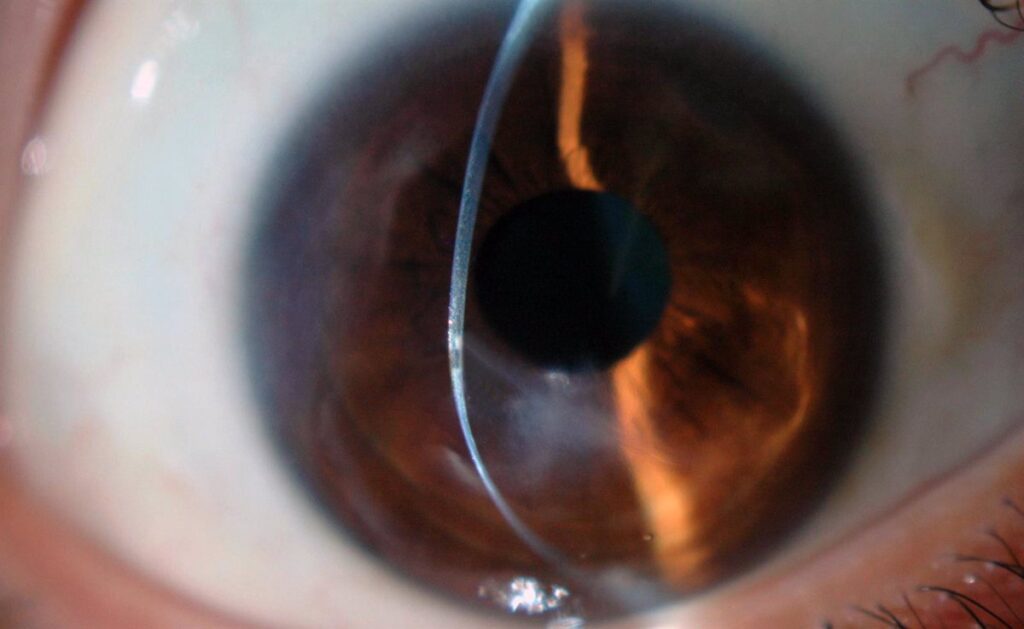

El queratocono: una enfermedad poco reconocida que impulsa la mayoría de los trasplantes de córnea en personas menores de 40 años.

El catedrático de Oftalmología e investigador de Honor de la Universidad Miguel Hernández (UMH) de Elche, el profesor Jorge Alió, ha advertido de que el queratocono, una patología poco conocida que debilita progresivamente la córnea, es la causa más frecuente de trasplante de córnea en menores de 40 años, todo ello de cara al día mundial de esta enfermedad, que se conmemora este domingo.

El queratocono se asocia a una deformación en forma de cono y su impacto es mayor en la cuenca mediterránea por su clima templado y floración frecuente y abundante. Su evolución empeora en áreas cálidas debido al frotamiento de los ojos causado por alergias, cuya frecuencia también es mayor en el mar Mediterráneo.

Entre los tratamientos propuestos por el doctor Alió se encuentran el uso de luz ultravioleta para endurecer la córnea, la cirugía con láser excimer para mejorar la regularidad corneal, el uso de segmentos corneales para moldear la córnea cuando está muy deformada, la utilización de láminas acelulares asociadas o no a células madre del propio paciente para tratar casos de córneas muy adelgazadas, y el trasplante de córnea con láser de femtosegundo.